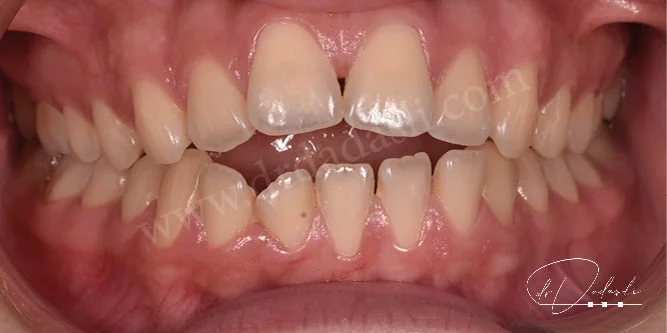

- Açık kapanış (Şekil 5 ve 6) – ağız kapatıldığı zaman alt ve üst ön dişler arasında boşluk kalmasıdır. Bazı olgularda arka taraftaki dişler arasında da açık kapanış olabilir.